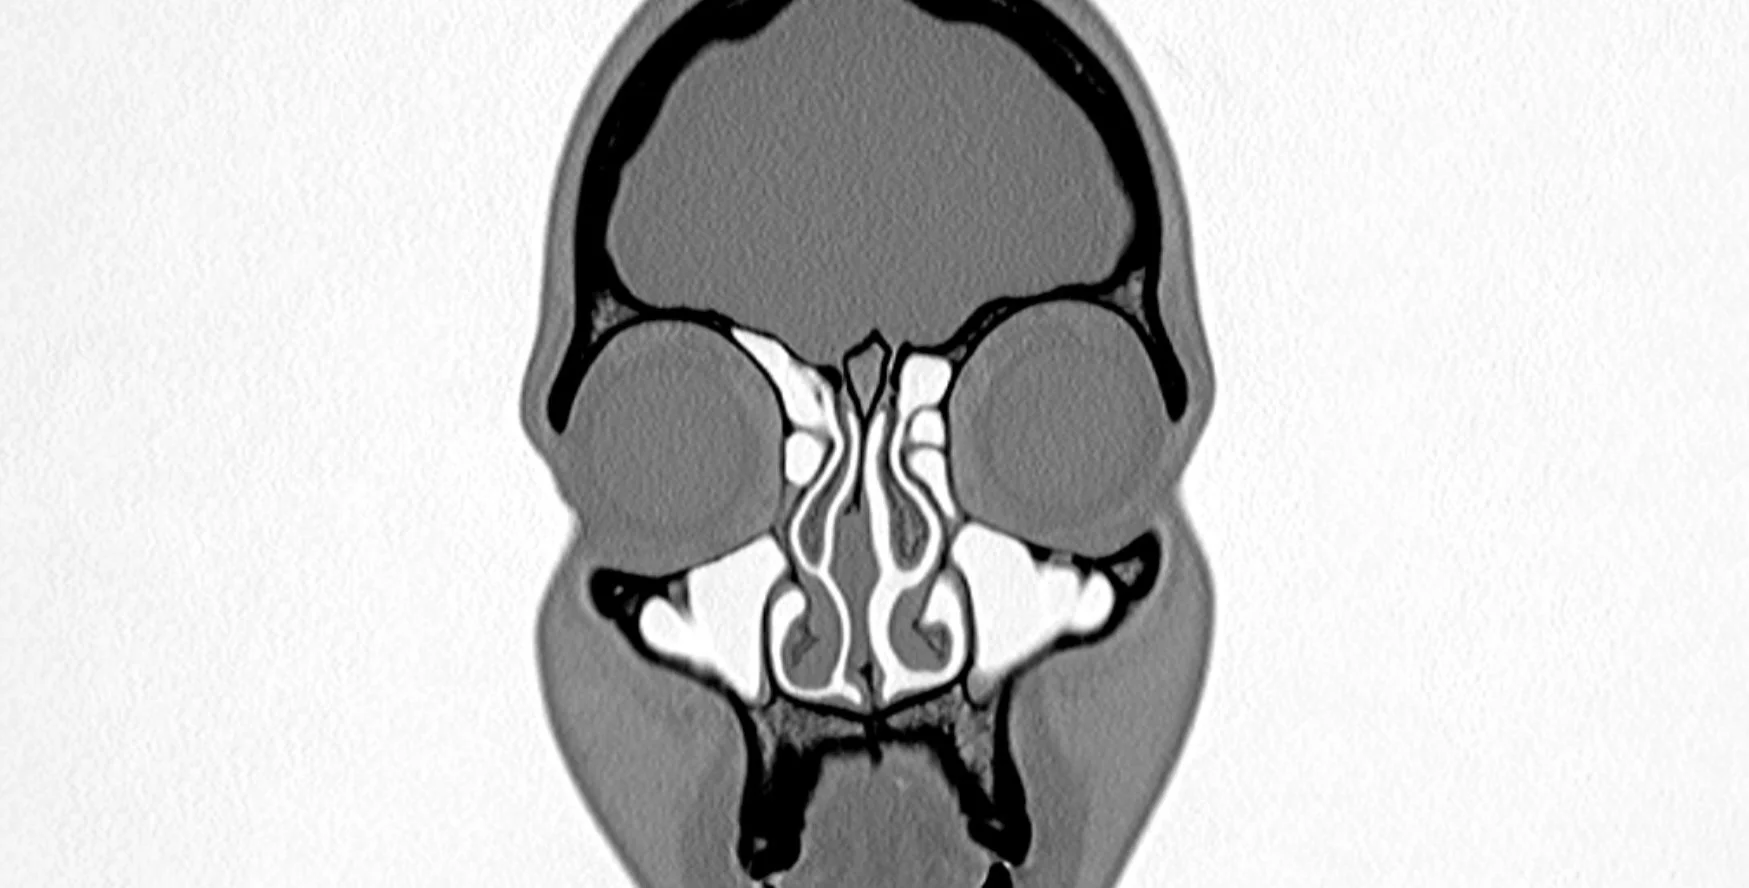

Anosmia

—Michelle Grabner